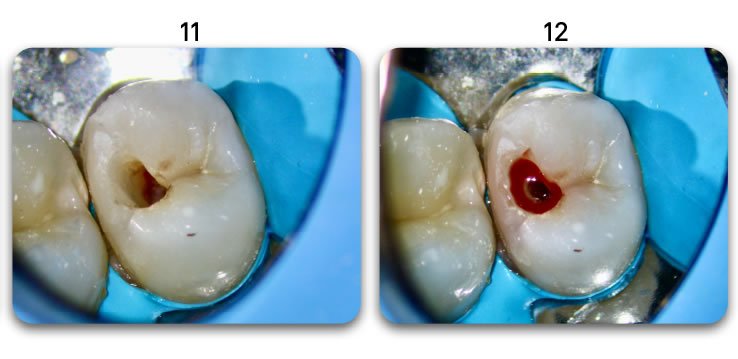

Excellent light transmission

Excellent light transmission for use with dual-cure resins, Biolight DUAL offer excellent light transmission through the optic fiber material.

It is important to follow the steps in the instructional video. There is a procedure that will ensure predictable, bubble-free results (see 1:57 in the video).